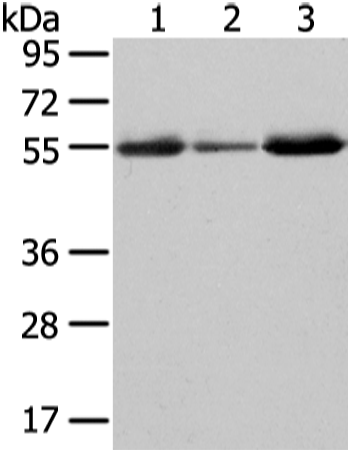

分类: 科研抗体货号: P12434别名: XKR2; XRG2; XPLAC应用: WB,IHC反应种属: Human